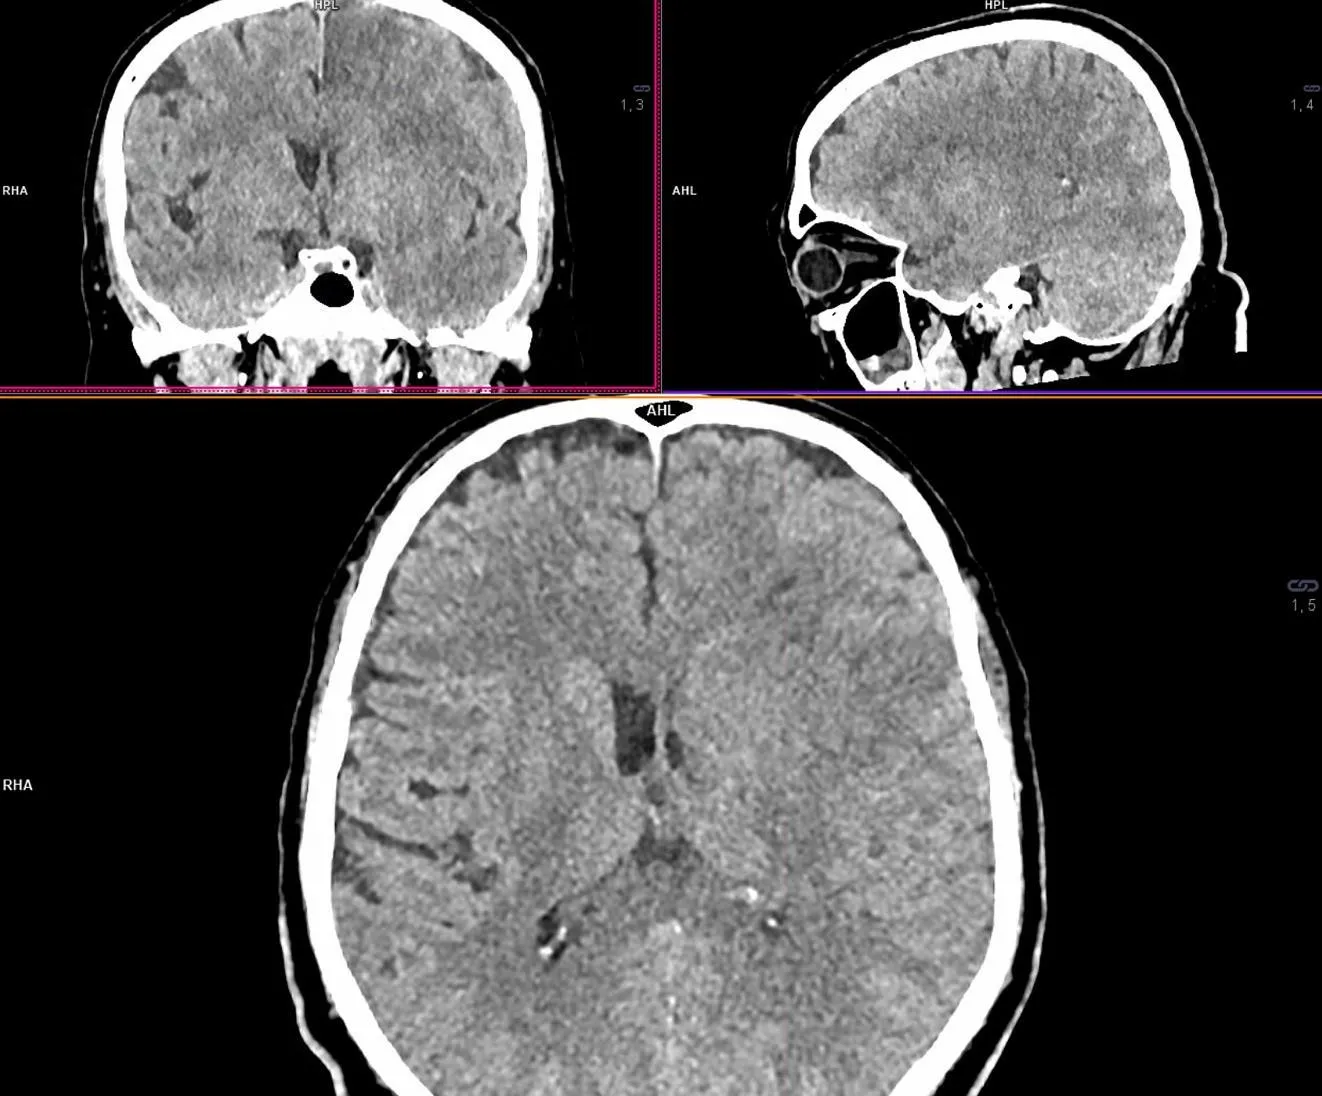

Повторна МСКТ голови була проведена 09.07.2022 близько 14:00 (44 години від початку захворювання, 22 години після пункції стегнової артерії), її результати наведені на рис. 9.

Рисунок 9. Повторна МСКТ головного мозку. Наразі визначається ефект запотівання від реперфузії ішемічного вогнища, із помірним зменшенням ступеня гіподенствності регіонів ішемічного ураження, особливо C, L, M1 і M4. Повторна оцінка за ASPECT = 5 балів. Ознак геморагічної трансформації вогнища інфаркту чи інших внутрішньочерепних крововиливів не виявлено.

Крім того, було поведене дослідження стану церебральних артерій за допомогою МСКТ- ангіографії (рис. 10).

Рисунок 10. Результати повторної МСКТ-ангіографії пацієнта Д.

Результати дослідження екстра- та інтракраніальних артерій продемонстрували відновлену прохідність (функціонуючий стент) проксимальної частини лівої ВСА (жовта стрілка) та нормальний просвіт лівої СМА в сегменті М1 (червона стрілка).

Повторне дослідження за допомогою МСКТ також дозволило виявити нове вогнище інфаркту мозку у басейні лівої передньої мозкової артерії та стенозування сегменту А2 ліворуч (рис. 11).

Рисунок 11. Ознаки стенозу лівої передньої мозкової артерії та інфаркту в її басейні, яких не

було при первинній нейровізуалізації.

Результати повторної МСКТ-ангіографії вказують на стенозування сегменту А2 лівої передньої мозкової артерії (жовта стрілка) та оклюзію калозомаргінальної артерії (червона стрілка). Результати повторної МСКТ голови продемонстрували нове вогнище інфаркту (червона стрілка) в парасагітальних відділах лівої лобної частки (басейн лівої передньої мозкової артерії).